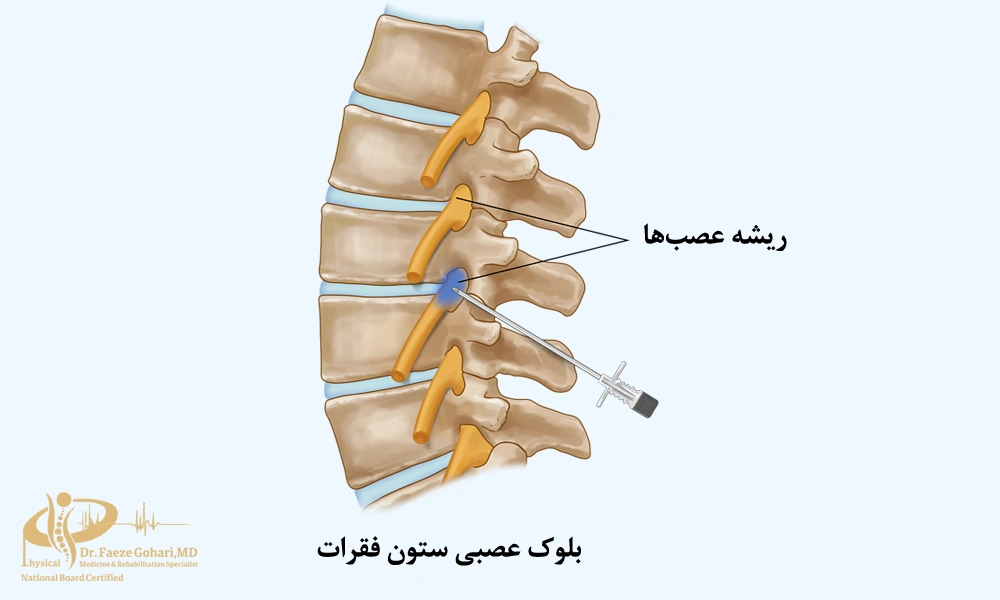

ستون فقرات (کمر و گردن)

در ستون فقرات، بلوک عصبی زمانی تجویز میشود که درد منشأ عصبی داشته باشد و درمانهای سادهتر (مانند داروهای خوراکی یا فیزیوتراپی) پاسخ کافی نداده باشند. هدف از این روش یا تسکین درد برای ادامه توانبخشی یا تشخیص منبع دقیق درد پیش از تصمیم به تجویز درمانهای تهاجمیتر است. این روش با تزریق دارو در اطراف اعصاب خاص، باعث کاهش سریع درد میشود و ماندگاری آن از چند هفته تا چند ماه متغیر است.

نحوه انجام بلوک عصبی ستونفقرات

نحوه انجام بلوک عصبی ستونفقرات در ادامه توضیح داده شده است:

- بلوک با تزریق دارو

در این روش، پزشک با کمک تصویربرداری (فلوروسکوپی) سوزن ظریف را در کنار عصب یا مفصل موردنظر قرار میدهد و داروهایی مانند بیحسی موضعی یا کورتون تزریق میکند. این داروها التهاب را کاهش میدهند و انتقال پیامهای درد را بهطور موقت متوقف میسازند. این روش معمولاً با بیحسی موضعی انجام میشود و بهجز سوزش مختصر یا فشار خفیف هنگام ورود سوزن و تزریق دارو، درد قابل توجهی ندارد. خود تزریق معمولاً ۱۵ تا ۳۰ دقیقه طول میکشد و اثر آن از چند روز تا چند ماه باقی میماند.